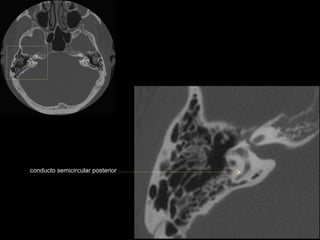

CATEDRA DE RADIOLOGIA U.N.L.P.   Hueso temporal normal        Edición 2002

conducto semicircular posterior